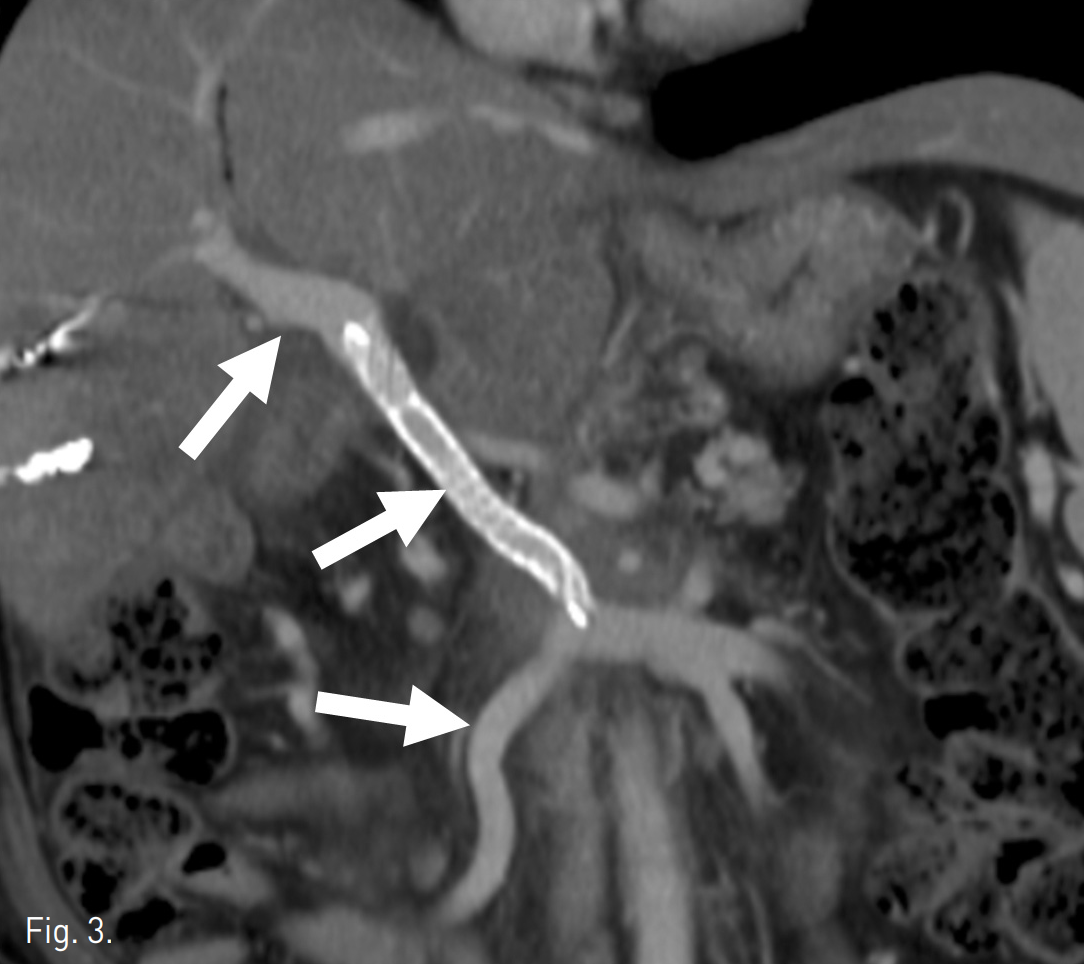

췌장의 팽대부주위 암종에 대한 췌장창자절제술(PPPD)후 문맥혈전이 생기는 빈도는 2% 내외로 보고 되고 있으나, 수술 후 방사선치료를 시행하거나 본 증례에서와 같이 합성혈관을 이용한 문맥재건술이 이뤄질 경우에 그 빈도는 13%~20%로 보고된 바 있다(1,2). 일반적으로 수술 후 합성혈관에 혈전이 발생할 경우 별다른 증상이나 이상소견이 나타나지 않으면 추적관찰을 하게 된다. 그러나 본 증례에서처럼 혈청 빌리루빈이나 간 효소수치가 상승하거나 CT 상에서 창자의 허혈이 의심될 때에는 허혈이나 경색으로 인한 창자절제를 피하기 위해 혈전용해술과 흡입혈전제거술을 시행할 수 있으며(3,4) 시술 시행 후 협착의 소견이 있거나 재발할 경우에 stent를 삽입한다(5,6). 보통 정맥에 stent-graft를 삽입하면 혈전의 재발로 인해 추가적인 시술을 요하는 경우가 많지만 문맥의 stent-graft는 1년의 추적관찰 후 75%~100%에서 개방성이 유지되었다는 보고가 있다(6,7). 문맥이나 위장간막동맥을 침범한 팽대부주위 암종으로 수술을 시행한 환자의 5년 사망률이 80%에 이르며, 이는 대부분 암종의 재발이나 전이에 의한 것이라는 사실에 비추어 문맥 내에 stent는 그 효용성이 큰 것으로 보인다. 본 증례에서는 6개월 후 추적관찰을 위한 CT를 시행하였으며, 문맥 내 stent의 개방성이 유지되고 있고 이와 관련한 다른 문제점은 발견되지 않았다(Fig. 3).

Fig. 3

Six months follow up CT scan shows the patency of the stent, portal and superior mesen teric veins (arrows). But, the size of residual pancreatic tumor wasincreased.